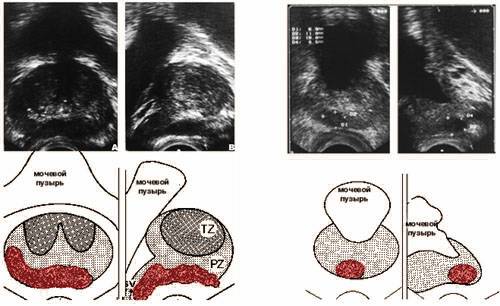

III.Ультразвуковое исследование (УЗИ) простаты, при показаниях - одновременно с биопсией.

![]() |